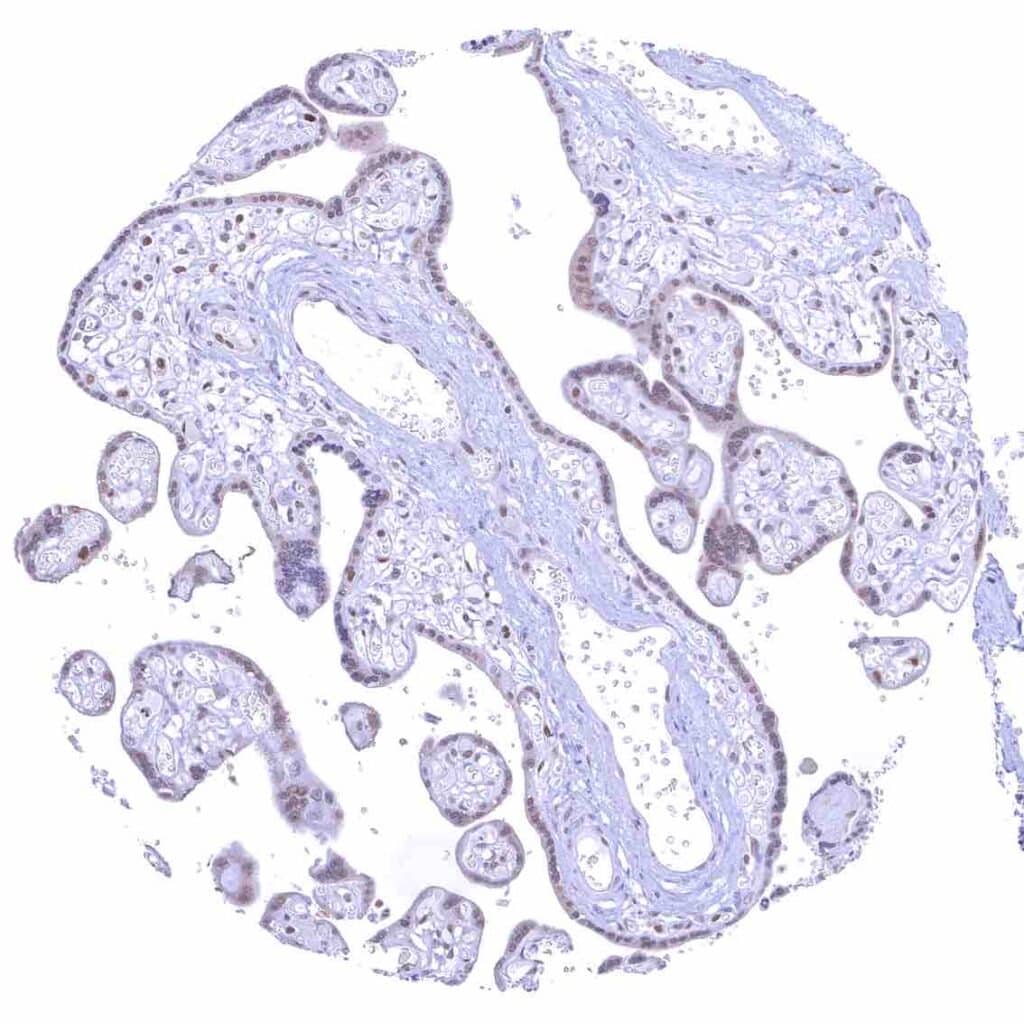

Tonsil – Strong nuclear p27 staining of a significant subset of cells, especially in the interfollicular area. Nuclear staining of squamous epithelial cells predominates in the more mature cell layers (top 50_ of the epidermis)

Tonsil, surface epithelium – Strong nuclear p27 staining of a significant subset of cells, especially in the interfollicular area. Nuclear staining of squamous epithelial cells predominates in the more mature cell layers (top 50_ of the epidermis)